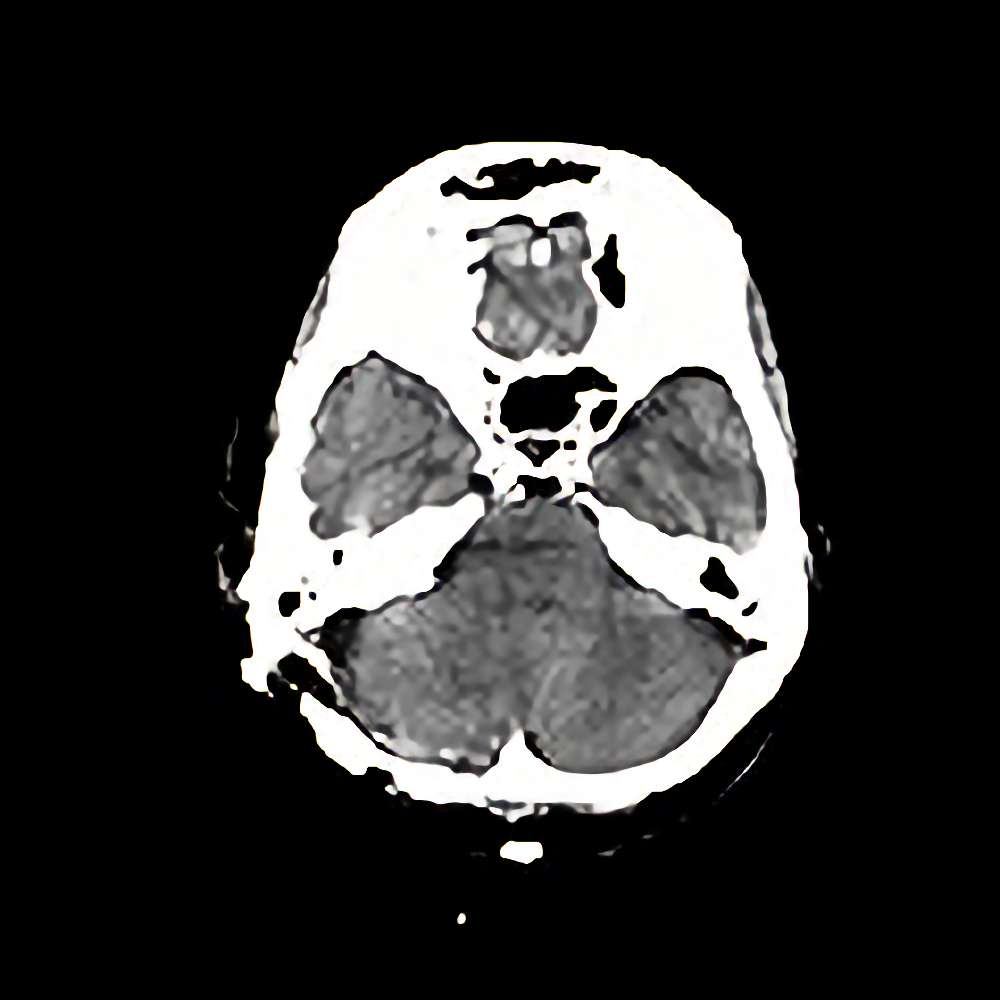

脳腫瘍

(小脳橋角部)

断層撮影

手術前1

No.’12_149 手術前1